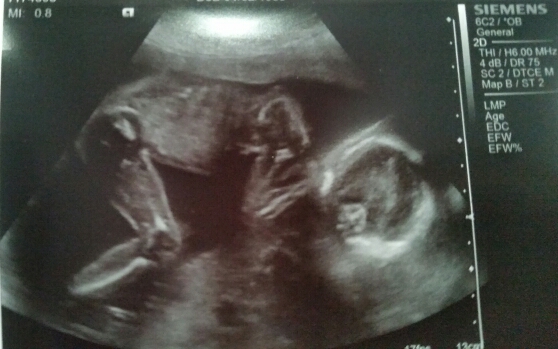

Petrified 16 week scan was wrong, 20 week scan in 2 days *UPDATE!